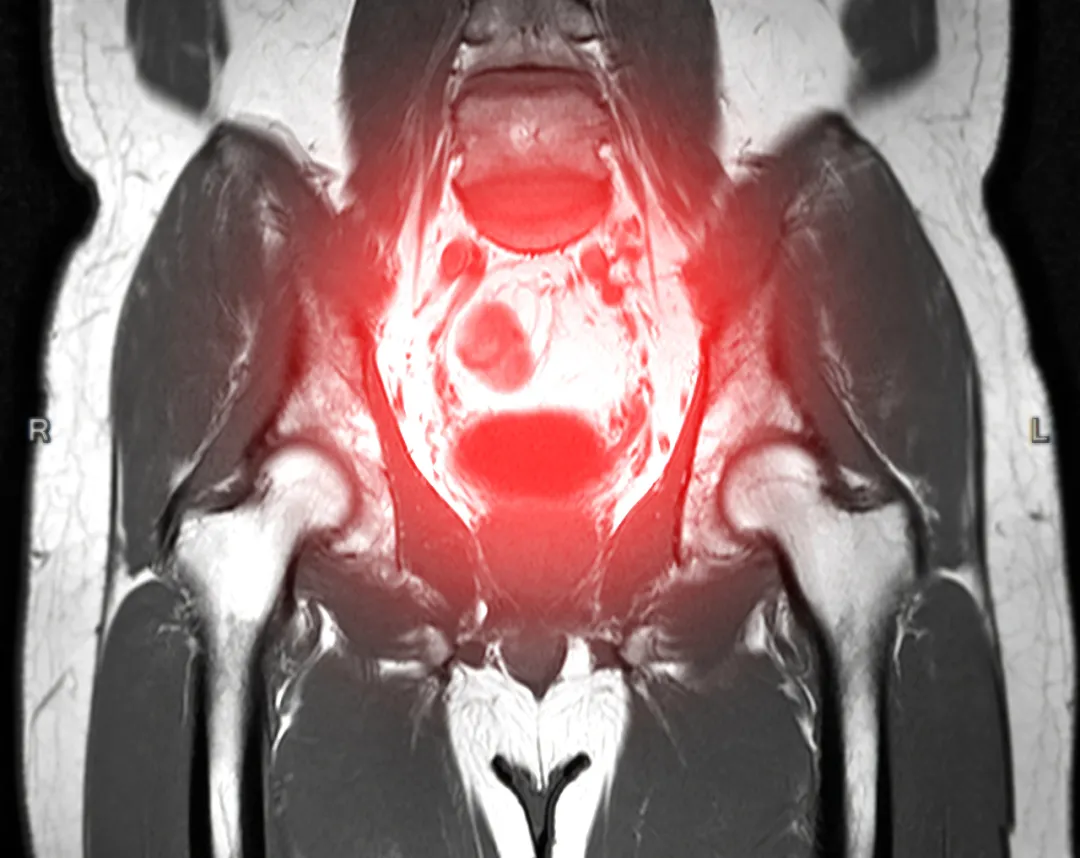

4、盆腔炎(PID)

女性上生殖道感染性疾病,累及子宫、输卵管、卵巢及盆腔腹膜,多由阴道炎、宫颈炎未及时控制引发。

5、子宫肌瘤

子宫平滑肌细胞增生形成的良性肿瘤,发病率随年龄增长升高,30-50岁女性中约20%-40%患病。